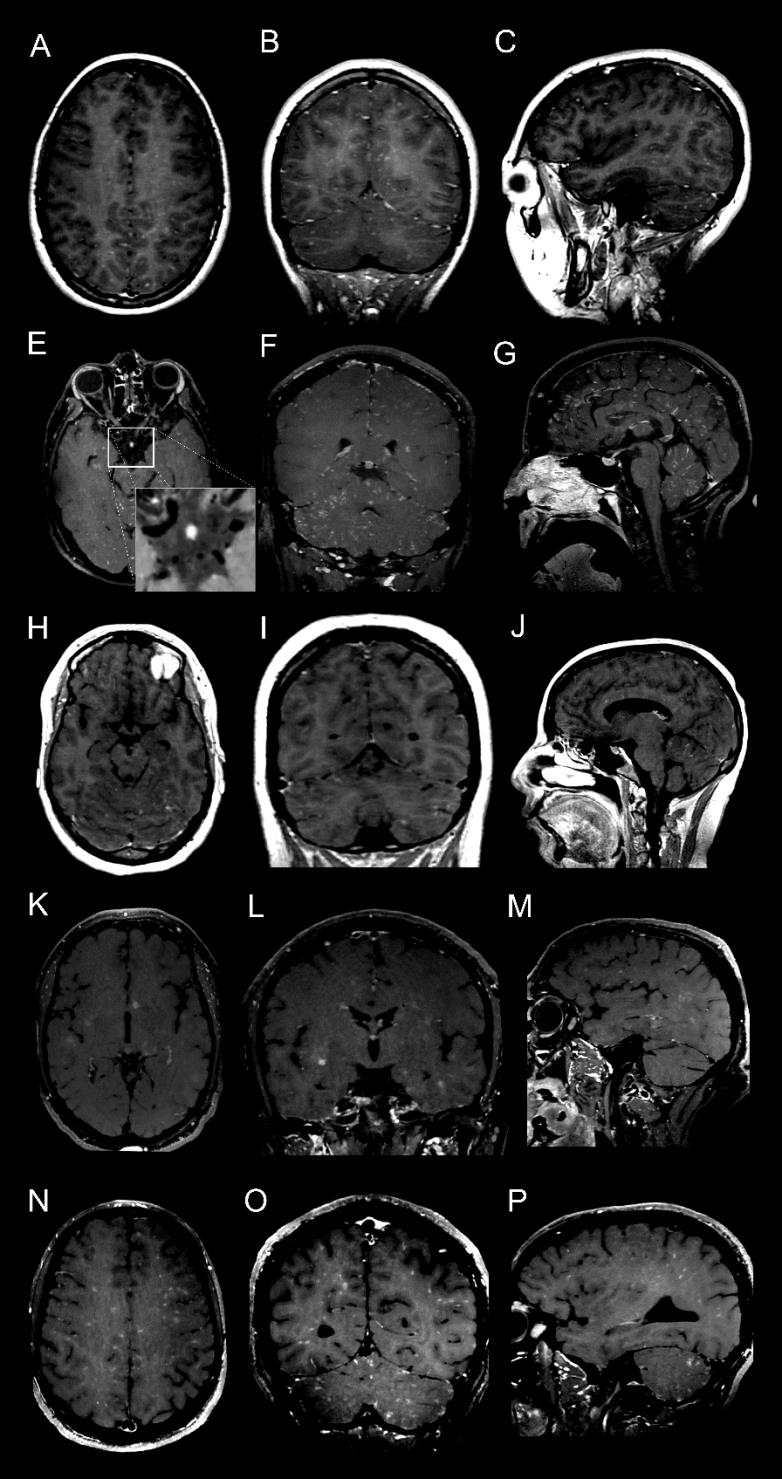

图4. 增强VW-MRI阳性结果总结。第1-5行分别显示了患者1-3、5和6。轴位(第一列)、冠状位(第二列)和矢状位(第三列)重建显示了主要发现。图像E中的插图,显示Willis环中没有血管壁增强